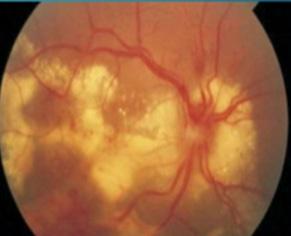

Uveitis posterior (Coreorretinitis)

ETIOLOGÍA

A menudo causado por una infección:

♦ Toxoplasmosis (Causa + común en inmunocompetentes)

♦ Virus (citomegalovirus → causa + común en inmunosuprimidos, infectados VIH)

♦ Sífilis

♦ Tuberculosis

♦ Histoplasmosis

♦ Enfermedad por arañazo de gato (unilateral)

♦ enfermedad de Lyme

Las causas no infecciosas incluyen enfermedad de Behçet (panuveitis recurrente remitente), LES, EII, poliangeítis y poliarteritis nodosa.

DIAGNÓSTICO

Alteraciones visuales indoloras. Disminución de la agudeza visual (visión borrosa).

Fondo de ojo

♦ Lesiones atróficas amarillentas (toxoplasma)

♦ Lesiones necróticas hemorrágicas (citomegalovirus)

TRATAMIENTO

Sulfadiazina + pirimetamina → toxoplasma

Ganciclovir o foscarnet → citomegalovirus

VHS → aciclvoir

Figura 41. Coreorretinitis por toxoplasma: Lesiones atróficas amarillentas Figura 42. Coreorretinitis por citomegalovirus: Lesiones necróticas hemorrágicas Figura 40. Toxoplasmosis es la causa más frecuente de coreorretinitis